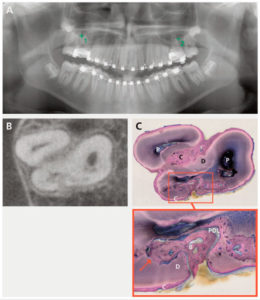

158 – Uso intraoperatorio de la CBCT para la identificación y localización de canales calcificados

Se sabe que la tomografía computarizada de haz cónico (CBCT) produce exploraciones tridimensionales de la dentición, las estructuras duras maxilofaciales y la relación de las